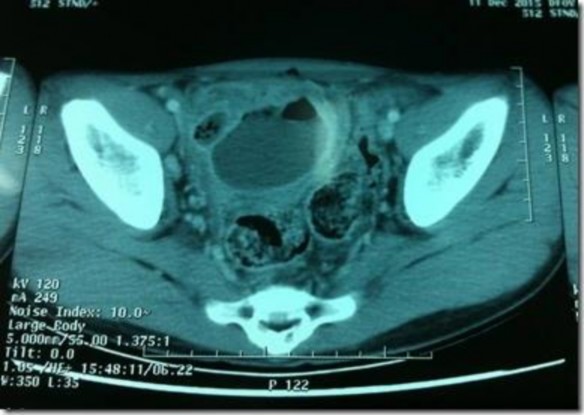

Hình 1.4 Hình ảnh áp xe ruột thừa trên CLVT

*Nguồn Dr Mohamed Saber [18]

Fluid collection is seen in the appendicular region with or without air within. Many times an appendicolith may be visualized [18] (Có thể thấy dịch tích tụ ở vùng ruột thừa kèm theo khí hoặc không. Có nhiều lúc có thể thấy cả sỏi).

Có hình ảnh ổ áp xe vùng hố chậu phải, hình ảnh ruột thừa viêm đã vỡ, đôi khi thấy có sỏi phân bên trong ổ áp xe.

Tốt nhất nên chụp có thuốc cản quang, chẩn đoán chính xác tình trạng ổ áp xe ruột thừa, đồng thời phân biệt được với các nguyên nhân khác.